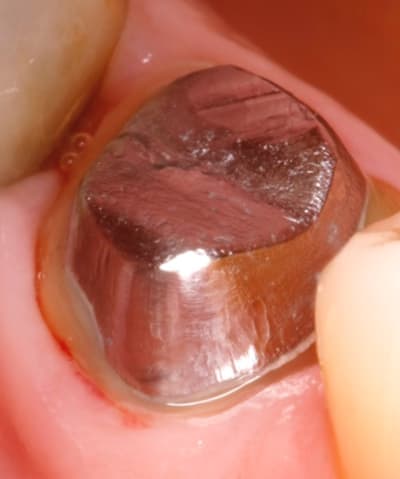

Sans aucun mauvais esprit, je trouve ton joint dent-inlay core très (trop) important ou alors c’est la photo macro qui ne pardonne rien?

putain , m' en parles pas , j'suis degouté .

ça encore ç est rien :-)

et tu crois qu ils sont brillants pourquoi ? pcq ils ne savent pas faire 1 forme qui va bien .donc je retaille de longue .

par exemple sur celui là dont tu parles , lorsque je l ai retaillé en bouche , le liseré est apparu .